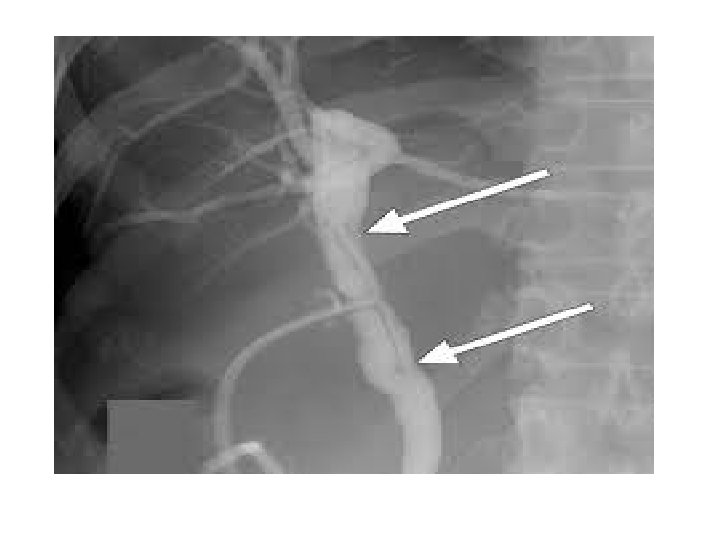

Prognosis With cholangiography, the bile ducts are visible on x-ray film. ERCP will show the pancreatic ducts as well. Obstruction within the bile duct system is identified by the lack of radiopaque contrast medium in a segment of the duct. Also, if there is obstruction, the bile ducts usually appear to have a larger diameter (dilated) than normal. Nonobstructed ducts are of normal size.

T-Tube cholangiography It is typically performed 5 to 10 days after gallbladder removal. Contrast dye is injected through a T-shaped rubber tube placed in the common bile duct during surgery, and x-rays are then taken to detect any residual stones or other abnormalities. The procedure will be explained to you and you will be asked to sign a consent form.

The individual lies in supine position) on X-ray table. The T-tube is cleaned by normal saline, approximately 5 ml of radiopaque contrast medium is injected into the T-tube, and x-ray images are taken. Additional contrast medium is usually injected (20 to 25 ml), and other x-rays are then taken as the individual is moved through a variety of positions on the table. A final xray is taken 15 minutes after the final injection of contrast medium to record the emptying of contrastladen bile into the duodenum. Postoperative cholangiography is not painful, although the individual may feel a bloating sensation in the upper right quadrant of abdomen as the contrast medium is injected.